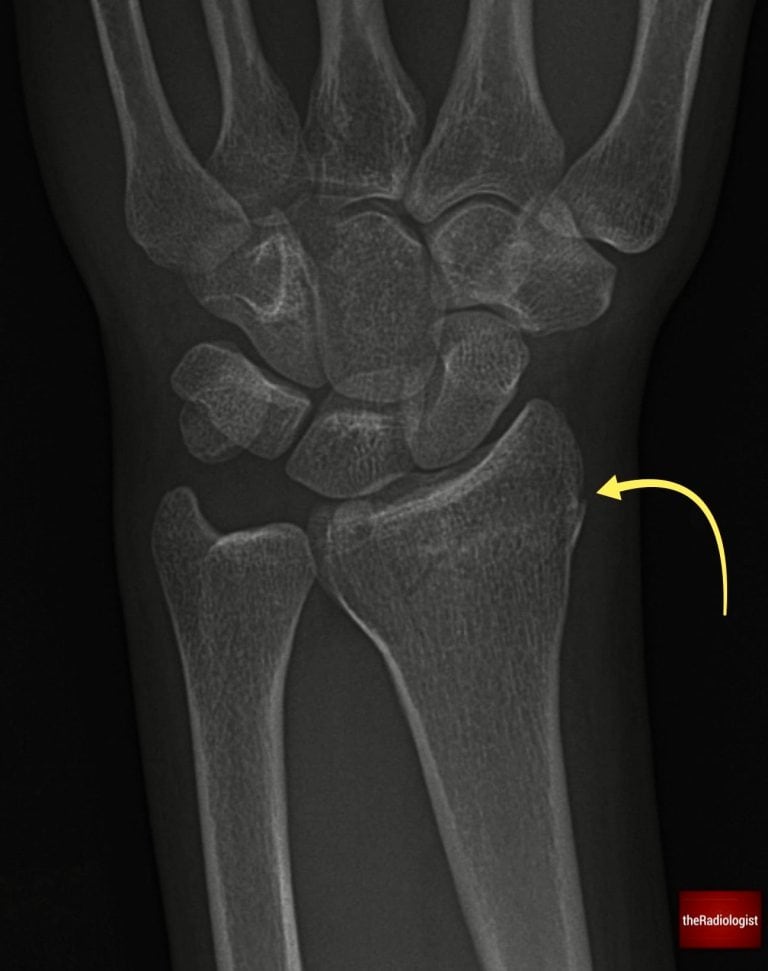

8. Radius and ulna

Finally, assess the distal radius and ulna. Look for cortical breaks or fracture lines, and check the relationship of their articular surfaces: the articular surface of the ulna should not sit distal to that of the radius. If it does, think about an impacted distal radial fracture or possible injury to the distal radioulnar joint. Ensure the distal radioulnar joint is intact and the radius and ulna are not separated: in the context of a radial fracture this could represent a Galeazzi fracture.

Scrutinise the distal radius and ulna looking for a break in the cortex or any suggestion of a fracture line which can be subtle. Here there is a distal radius fracture.